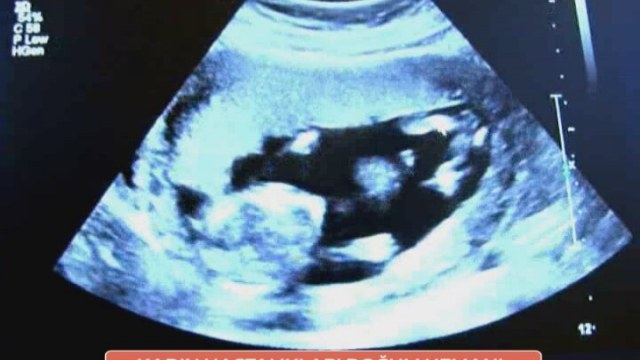

Kaç Haftalık Hamileyim? İşte gebelik haftası hesaplama...